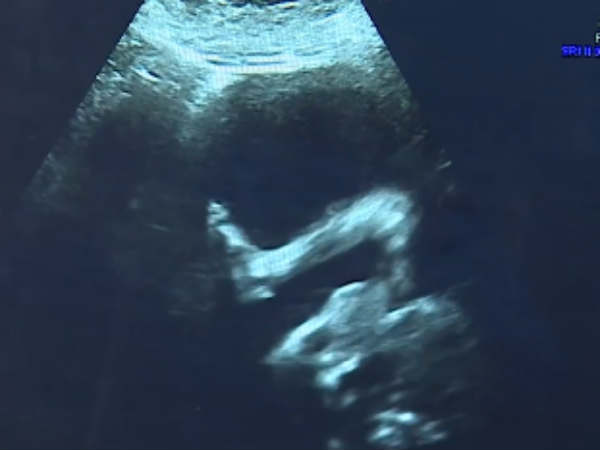

கருவில் இருந்த சிசுவுக்கு முதுகெலும்பு ஆபரேஷன்.. லண்டன் மருத்துவர்கள் புதிய சாதனை

கருவில் உள்ள குழந்தைக்கு முதுகெலும்பு ஆபரேஷன் செய்து லண்டன் மருத்துவர்கள் சாதனை புரிந்துள்ளனர்.

இங்கிலாந்து தலைநகர் லண்டனில் உள்ள மேற்கு சாசெக்ஸ் பகுதியைச் சேர்ந்தவர் ஷெர்ரி ஷார்ப் (29). கர்ப்பிணியான இவர் 20 வாரங்களில் வழக்கமான மருத்துவ பரிசோதனைக்காகச் சென்றுள்ளார். அப்போது ஸ்கேனில் கருவில் இருந்த குழந்தையின் முதுகெலும்பு சீராக இல்லை என்ற அதிர்ச்சித் தகவல் தெரிய வந்துள்ளது. இதனால் எதிர்காலத்தில் அக்குழந்தையால் நடக்க இயலாமல் போகும் அபாயம் இருந்தது.

இதையடுத்து 27 வாரங்கள் ஆன நிலையில், கருவில் இருந்த அக்குழந்தைக்கு மருத்துவர்கள் அறுவைச் சிகிச்சை செய்துள்ளனர். மருத்துவர்களின் திறமையால் அந்த அறுவைச் சிகிச்சை வெற்றிகரமாக முடிந்தது.